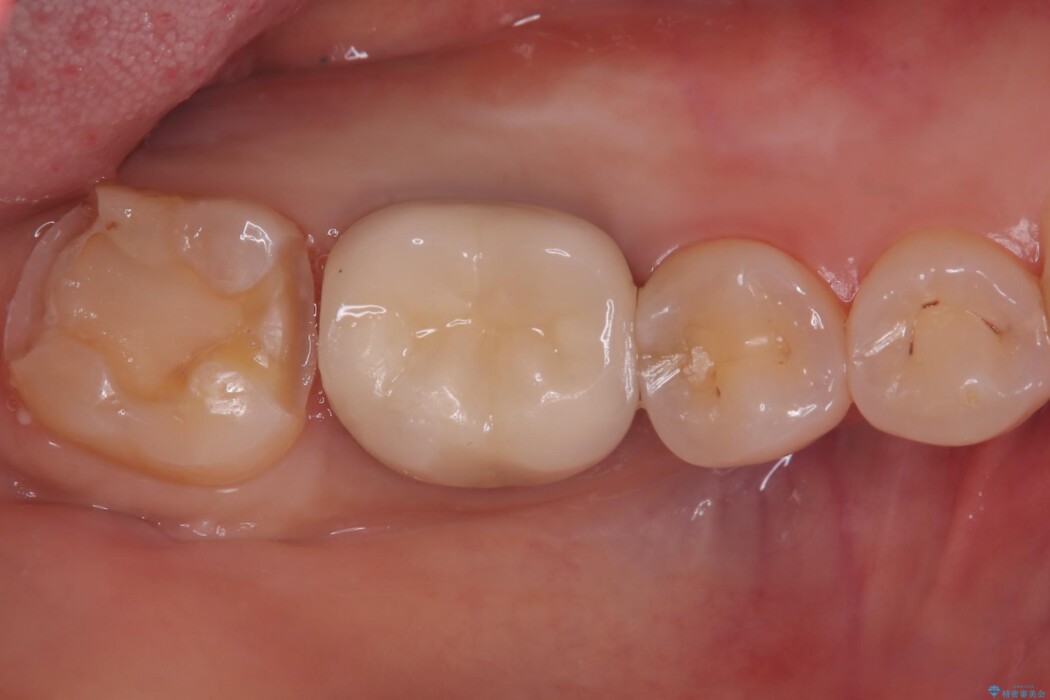

右下奥歯の広範囲な虫歯と劣化した古い詰め物をすべて除去し、新しくセラミックインレーで修復しました。装着時にはラバーダムを使用し、湿気を遮断した状態で精密に接着させています。